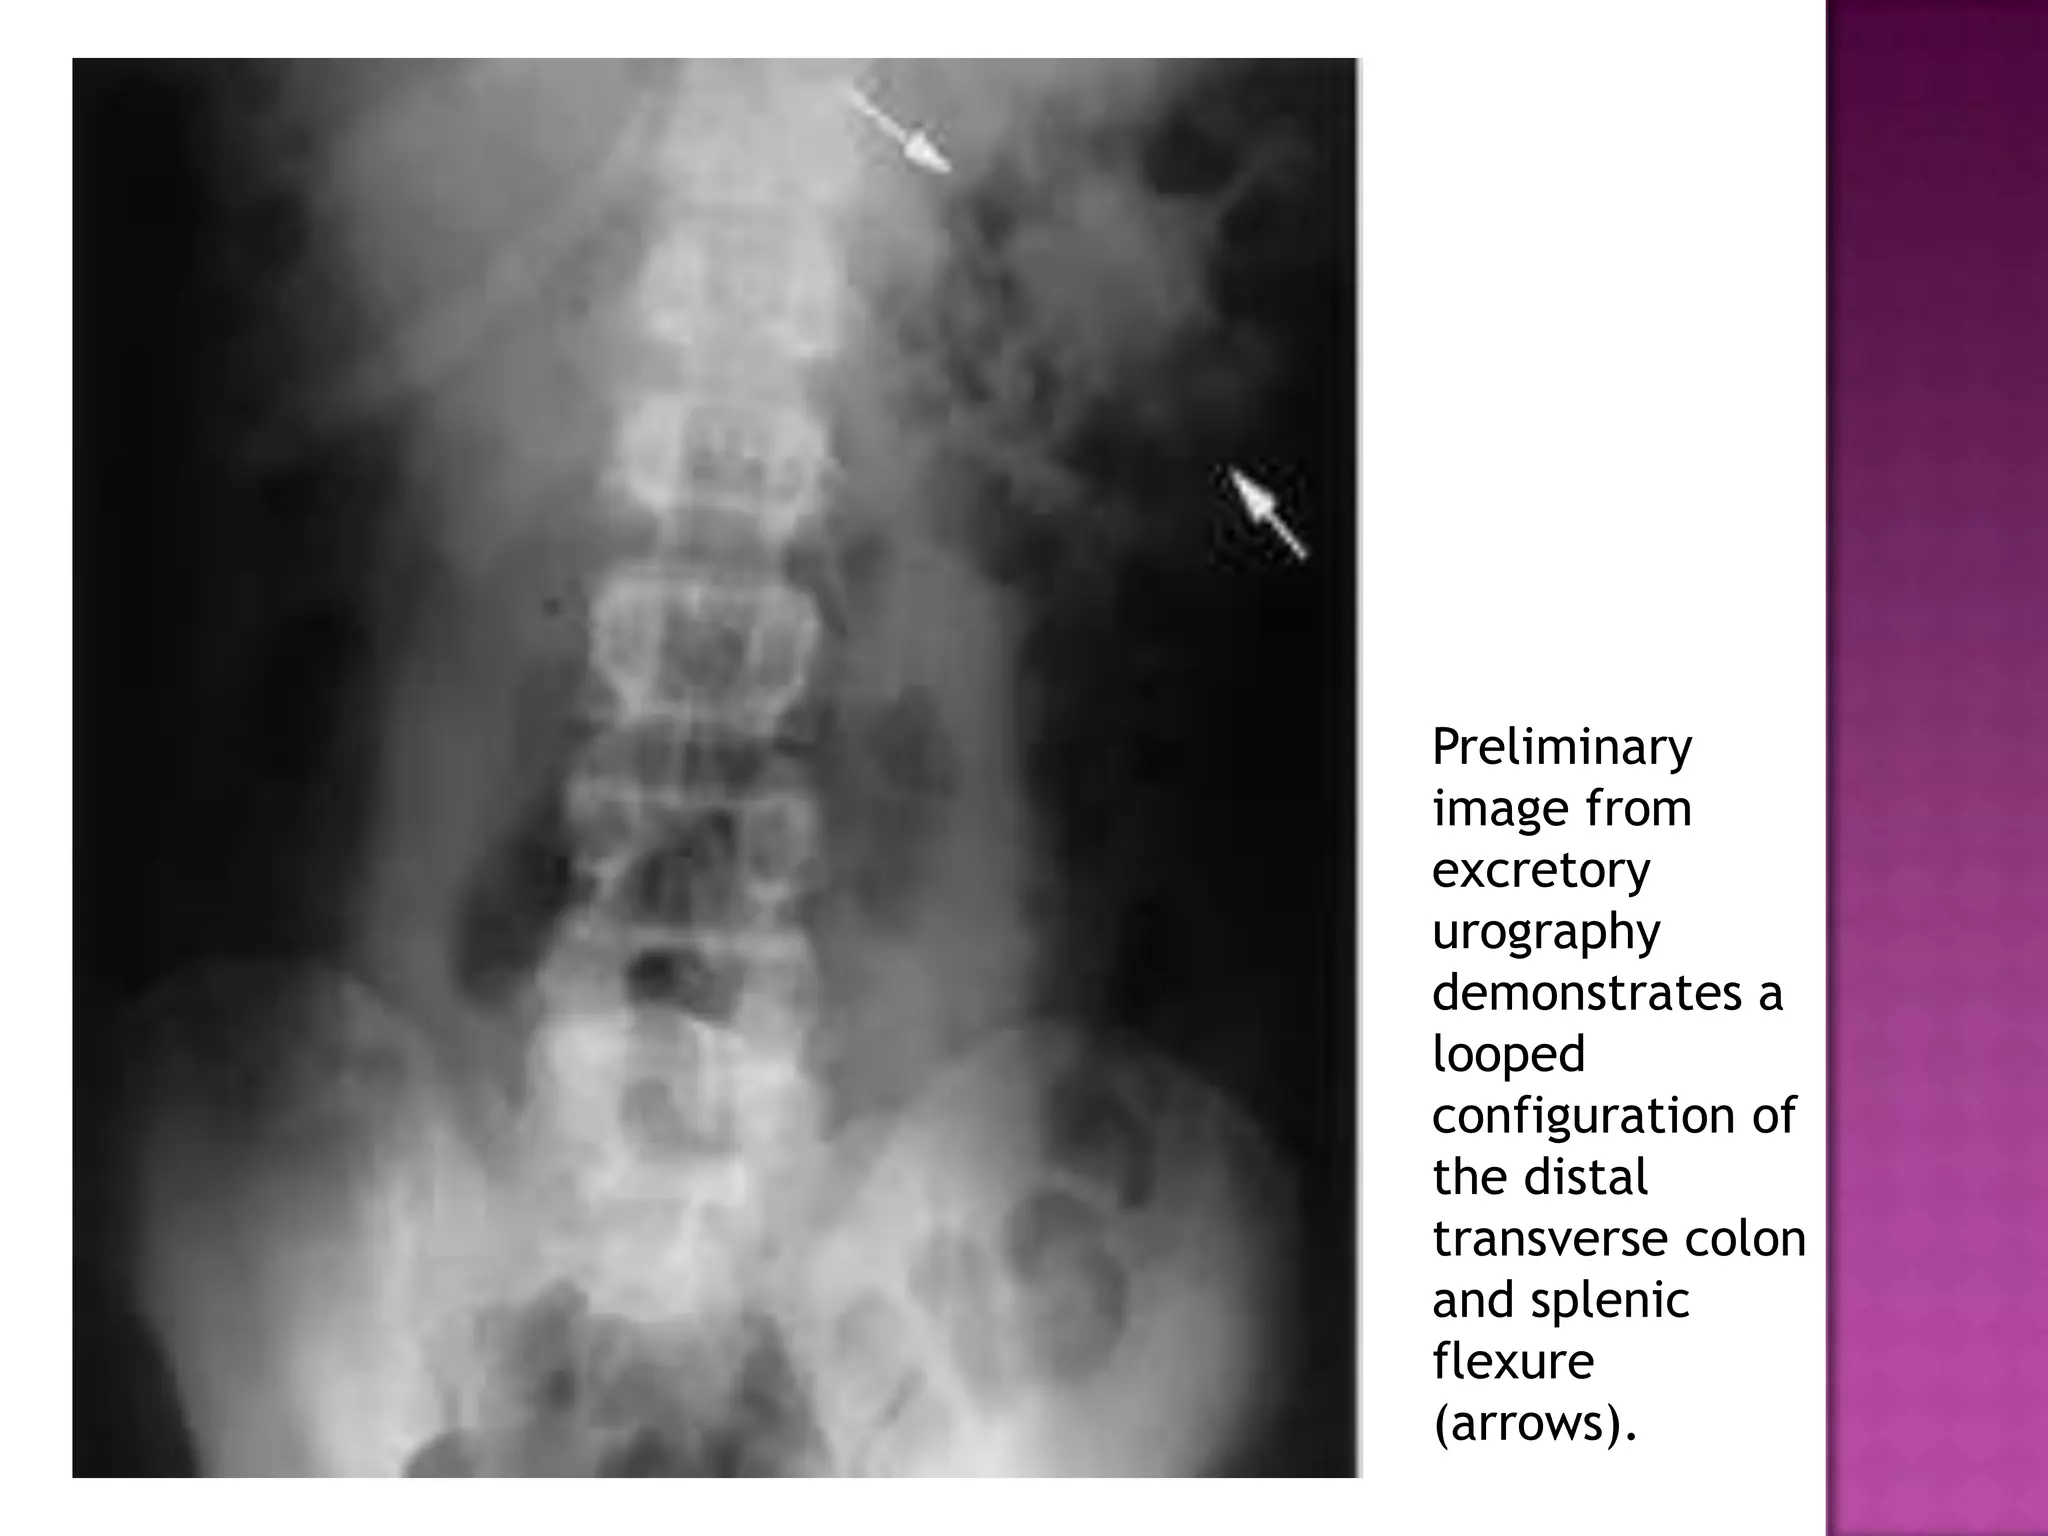

Preliminary

image from

excretory

urography

demonstrates a

looped

configuration of

the distal

transverse colon

and splenic

flexure

(arrows).

Preliminary image from excretory urography demonstrates a looped configurationof the distal transverse colon and splenic flexure (arrows).